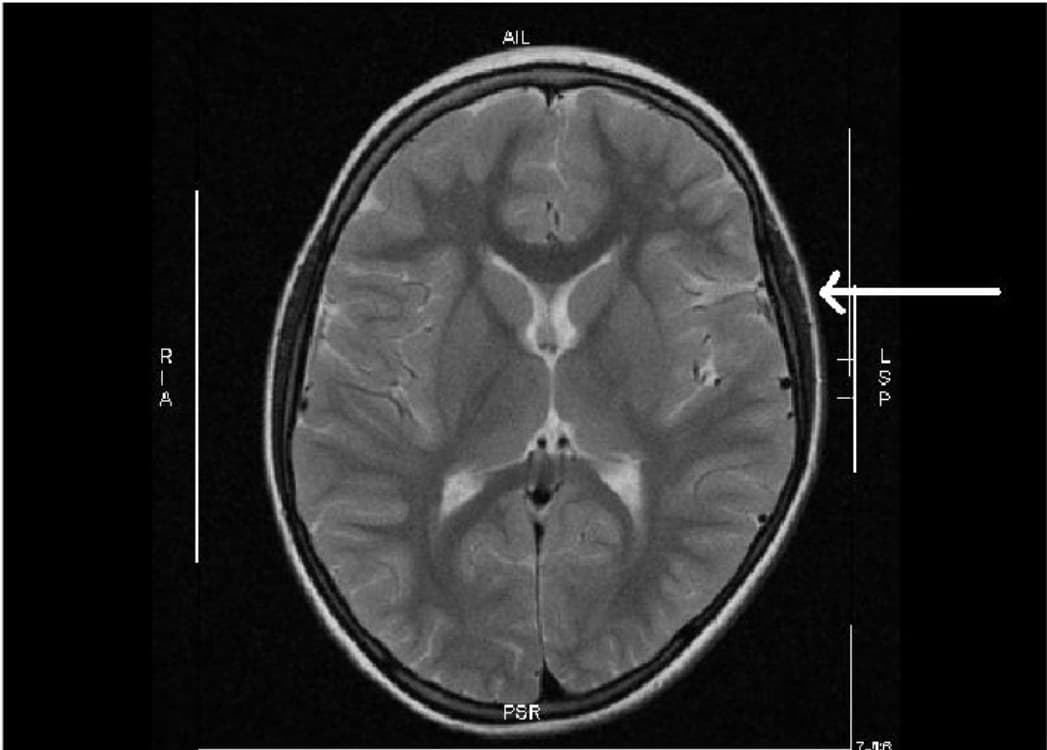

Según la WebMD, la encefalopatía abarca un grupo de trastornos que representan "un problema de salud grave que, sin tratamiento, puede causar daño cerebral temporal o permanente". No debe confundirse con la encefalitis, que es una inflamación del cerebro.

Estos problemas ocurren cuando ha habido un cambio en la forma en que funciona el cerebro o un cambio en el cuerpo que afecta el cerebro, especifica la web médica. Esos cambios conducen a un estado mental alterado y dejan al paciente confundido y sin poder actuar como lo ha hecho normalmente.

"La encefalopatía, que se caracteriza por una función mental alterada que va desde una confusión leve hasta el coma, es la manifestación neurológica más grave del covid-19", dijo el doctor Igor Koralnik, profesor de neurología de la Universidad de Northwestern y uno de los autores del estudio, citado por Bloomberg.

Los científicos descubrieron que los pacientes con encefalopatía no solo son menos capaces de cuidarse a sí mismos sino que también tienen muchas más probabilidades de morir dentro de los 30 días posteriores al ingreso en el hospital (21.7% de probabilidades frente al 3.2% en pacientes que no presentaron este síntoma).

"Las manifestaciones neurológicas ocurren en la mayoría de los pacientes hospitalizados con covid-19", concluye el estudio. "La encefalopatía se asoció con una mayor morbilidad y mortalidad, independientemente de la gravedad de la enfermedad respiratoria", agregó la investigación.